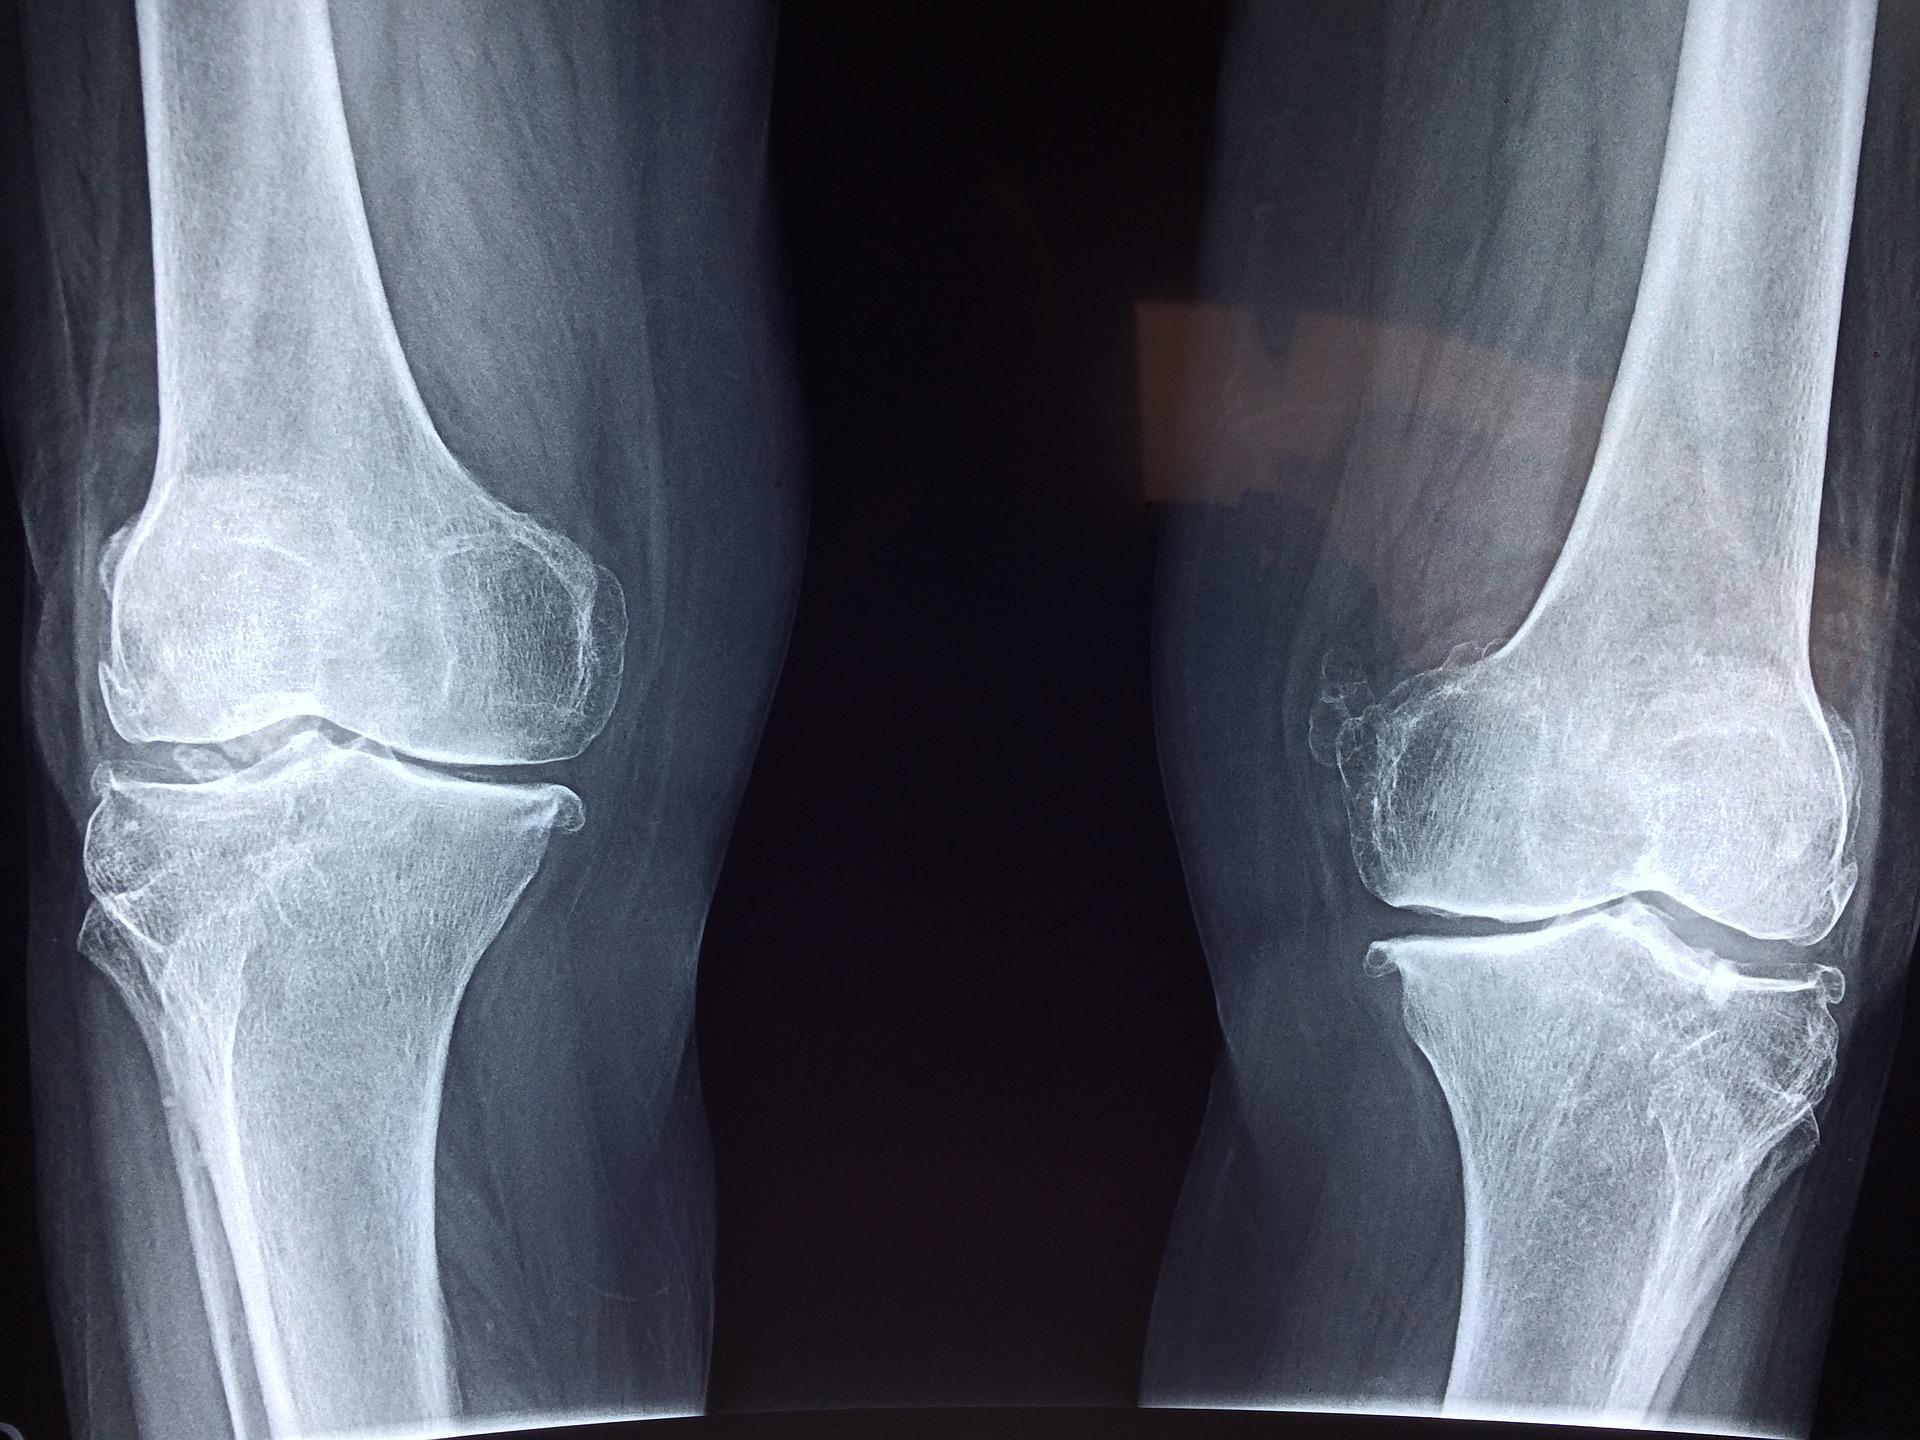

Schwache Muskeln erhöhen Arthroserisiko. Stimmt das?

Update einer Meta-Analyse entkräftet bisherige Erkenntnisse.

Kniearthrose ist einer der häufigsten Gründe für einen operativen Eingriff. Eine Vielzahl von WissenschaftlerInnen befassen sich mit der Suche nach Risikofaktoren für den frühzeitigen Gelenkverschleiß.

Der Gelenkverschleiß ist eine physiologische Alterserscheinung. Ähnlich den grauen Haaren und Falten. Der „Normalzustand“ der Arthrose ist die schmerzfreie, uneingeschränkte Funktionsfähigkeit. Denn die Mehrheit der Menschen weist eine radiologische Arthrose auf, ohne Beschwerden zu haben (Quelle). Es gibt eine Vielzahl von Mechanismen, die letztlich den Unterschied zwischen einer klinisch auffälligen und einer asymptomatischen Arthrose machen können (Quelle).